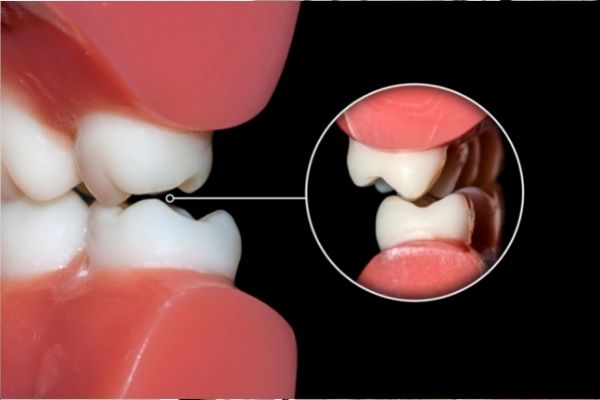

– Mordida cruzada: Los dientes superiores están más hacia dentro en comparación a los inferiores. Algo totalmente contrario a lo que debería de ser ya que los superiores deberían de estar un poco más hacia fuera.

– Mordida en tijera: Esta maloclusión es muy notable ya que las piezas dentales de la zona superior están totalmente por fuera de las inferiores.